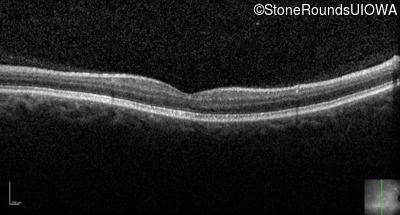

Optical Coherence Tomography - Right - 20/200

Exemplar / OCT Stack

OCT Stack